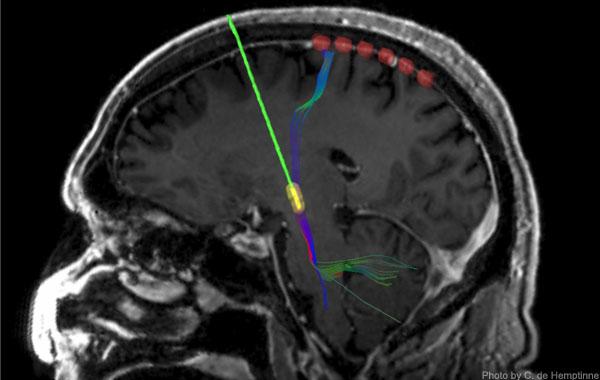

During surgery on 23 patients with Parkinson's disease in whom permanent DBS electrodes were being surgically implanted, the UCSF team slid a temporary strip of 6 recording electrodes under the skull and placed it over the motor cortex. As in the prior research, recordings of neural activity showed excessive synchronization of activity rhythms in the patients.

As the name of the therapy implies, the end of the stimulating lead of DBS devices is placed in a structure deep in the brain known as the subthalamic nucleus (STN), which is part of a "loop" of neural circuitry that includes the motor cortex on the brain's surface. When the DBS device was activated and began stimulating the STN, the effect of the stimulation reached the motor cortex, where over-synchronization rapidly diminished. If the device was turned off, excessive synchrony re-emerged, more gradually in some patients than others.

DBS surgery generally takes about six hours, and during the middle of the procedure patients are awakened for testing of the device and to ensure that the stimulating lead is properly placed in the STN. During this period the researchers asked 12 of the patients to perform a reaching task in which they had to touch a blue dot appearing on a computer screen. Importantly, said Starr, recordings revealed that DBS eliminated excessive synchrony of motor cortex activity and facilitated movement without altering normal changes in brain activity that accompany movements.